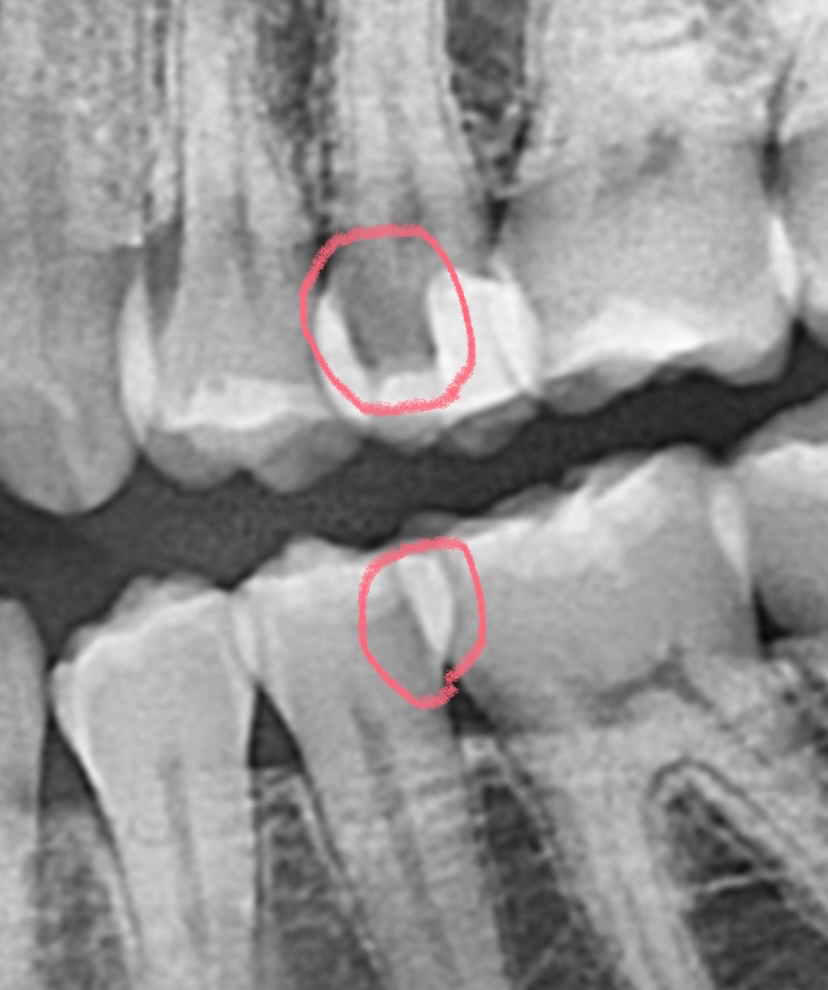

방사선사진으로만 본다면 아래치아는 충치의 가능성이 높습니다.

위의 치아는 충치일수도 있고, 단순히 방사선흑화도가 높아서 그렇게 보이는것일수도 있습니다

정확한 판단을 위해선 눈으로 직접 검사를 해봐야 알 수 있을 것으로 보입니다. 감사합니다.

말씀하신 부위 모두 충치입니다. 방사선 사진을 촬영할 때, tearing 된 부위도 비슷하게 보이나 현재 치아가 겹쳐져 있는 상태에서 지금과 같은 정도의 radiolucency를 보인다면 이는 충치일 가능성이 매우 높습니다. 따라서 치료를 해야할 것으로 보이며 신경과도 어느정도 근접하므로 신경치료의 가능성도 열어두셔야 합니다.

사진상으로 보이는 부분은 충치는 아닌거 같습니다. 일종의 파노라마 사진의 오류일꺼 같습니다. 정확한건 눈으로 직접보거나 작은 사진을 찍어보면 알수 있습니다.